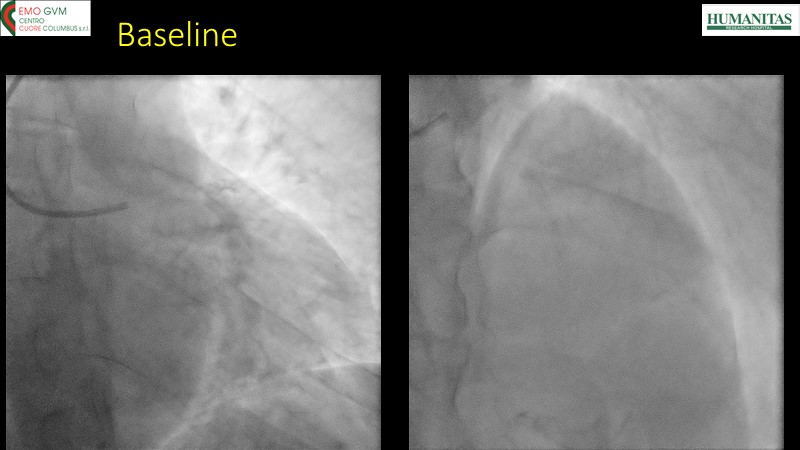

- To know why sirolimus coated balloon is the ideal choice in native vessel disease treatment through a case presentation